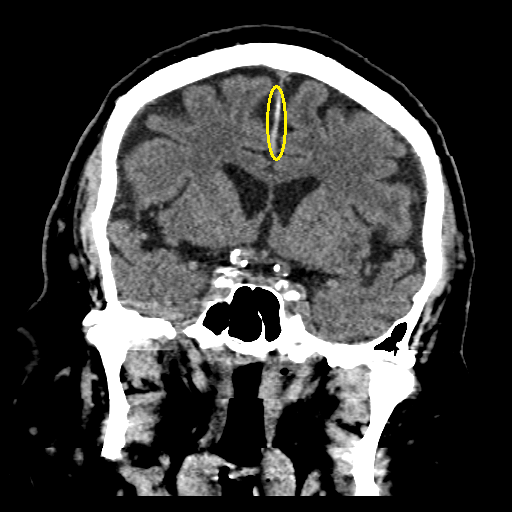

brain CT의 coronal view이다. 앞쪽 사진은 정상적인 falx의 모습을 보이고 있으나 뒤쪽 사진은 비후 된 falx의 모양을 확인할 수 있다.

brain CT의 axial view이다. 좌우 반구를 나누는 가운데 가느다란 falx 중 일부가 두꺼워져 보인다. 바로 falx를 따라 생기는 falx SDH(subdural hematoma)의 소견이다.